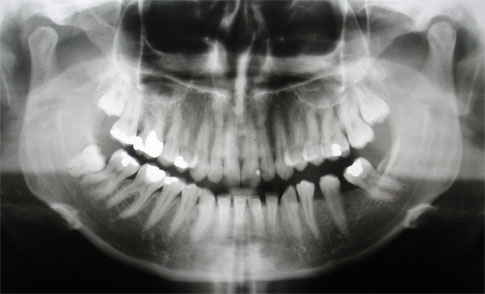

I modelli dentali sono delle riproduzioni di arcate dentali. È possibile distinguere i modelli in: modelli da archivio: fissa un momento clinico irripetibile in senso diagnostico e storico. Tale manufatto accuratamente elaborato entra nella...